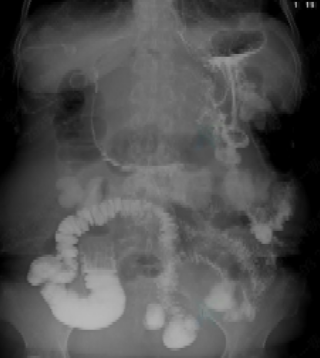

术后第二天胃肠道泛影葡胺造影显示支架通畅,造影剂沿支架流入小肠,小肠显影充分